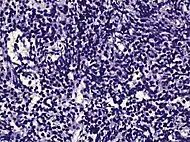

| Intraductal adenocarcinoma | 2.8%[10] | ![]() H&E and CK5/6 |

|||||

Intraductal carcinoma

Intraductal carcinoma of the prostate gland (IDCP), which is now categorised as a distinct entity by WHO 2016, includes two biologically distinct diseases. IDCP associated with invasive carcinoma (IDCP-inv) generally represents a growth pattern of invasive prostatic adenocarcinoma while the rarely encountered pure IDCP is a precursor of prostate cancer.[19] The diagnostic criterion of nuclear size at least 6 times normal is ambiguous as size could refer to either nuclear area or diameter. If area, then this criterion could be re-defined as nuclear diameter at least three times normal as it is difficult to visually compare area of nuclei.[19] It is also unclear whether IDCP could also include tumors with ductal morphology.[19] There is no consensus whether pure IDCP in needle biopsies should be managed with re-biopsy or radical therapy. A pragmatic approach would be to recommend radical therapy only for extensive pure IDCP that is morphologically unequivocal for high-grade prostate cancer.[19] Active surveillance is not appropriate when low-grade invasive cancer is associated with IDCP, as such patients usually have unsampled high-grade prostatic adenocarcinoma.[19] It is generally recommended that IDCP component of IDCP-inv should be included in tumor extent but not grade.[19] However, there are good arguments in favor of grading IDCP associated with invasive cancer.[19] WHO 2016 recommends that IDCP should not be graded, but it is unclear whether this applies to both pure IDCP and IDCP-inv.[19]

Intraductal carcinoma of the prostate with an infiltrative growth pattern may be morphologically difficult to distinguish from invasive cancer. One focus shows comedonecrosis (arrow), morphologically suggesting Gleason pattern 5 invasive carcinoma (a haematoxylin and eosin, b CK5/6)[19]

Intraductal carcinoma of the prostate with very patchy basal cells identified by immunohistochemistry. At least some of the glands lacking basal cell immunoreactivity represent intraductal rather than invasive carcinoma (a haematoxylin and eosin, b CK 5/6)[19]